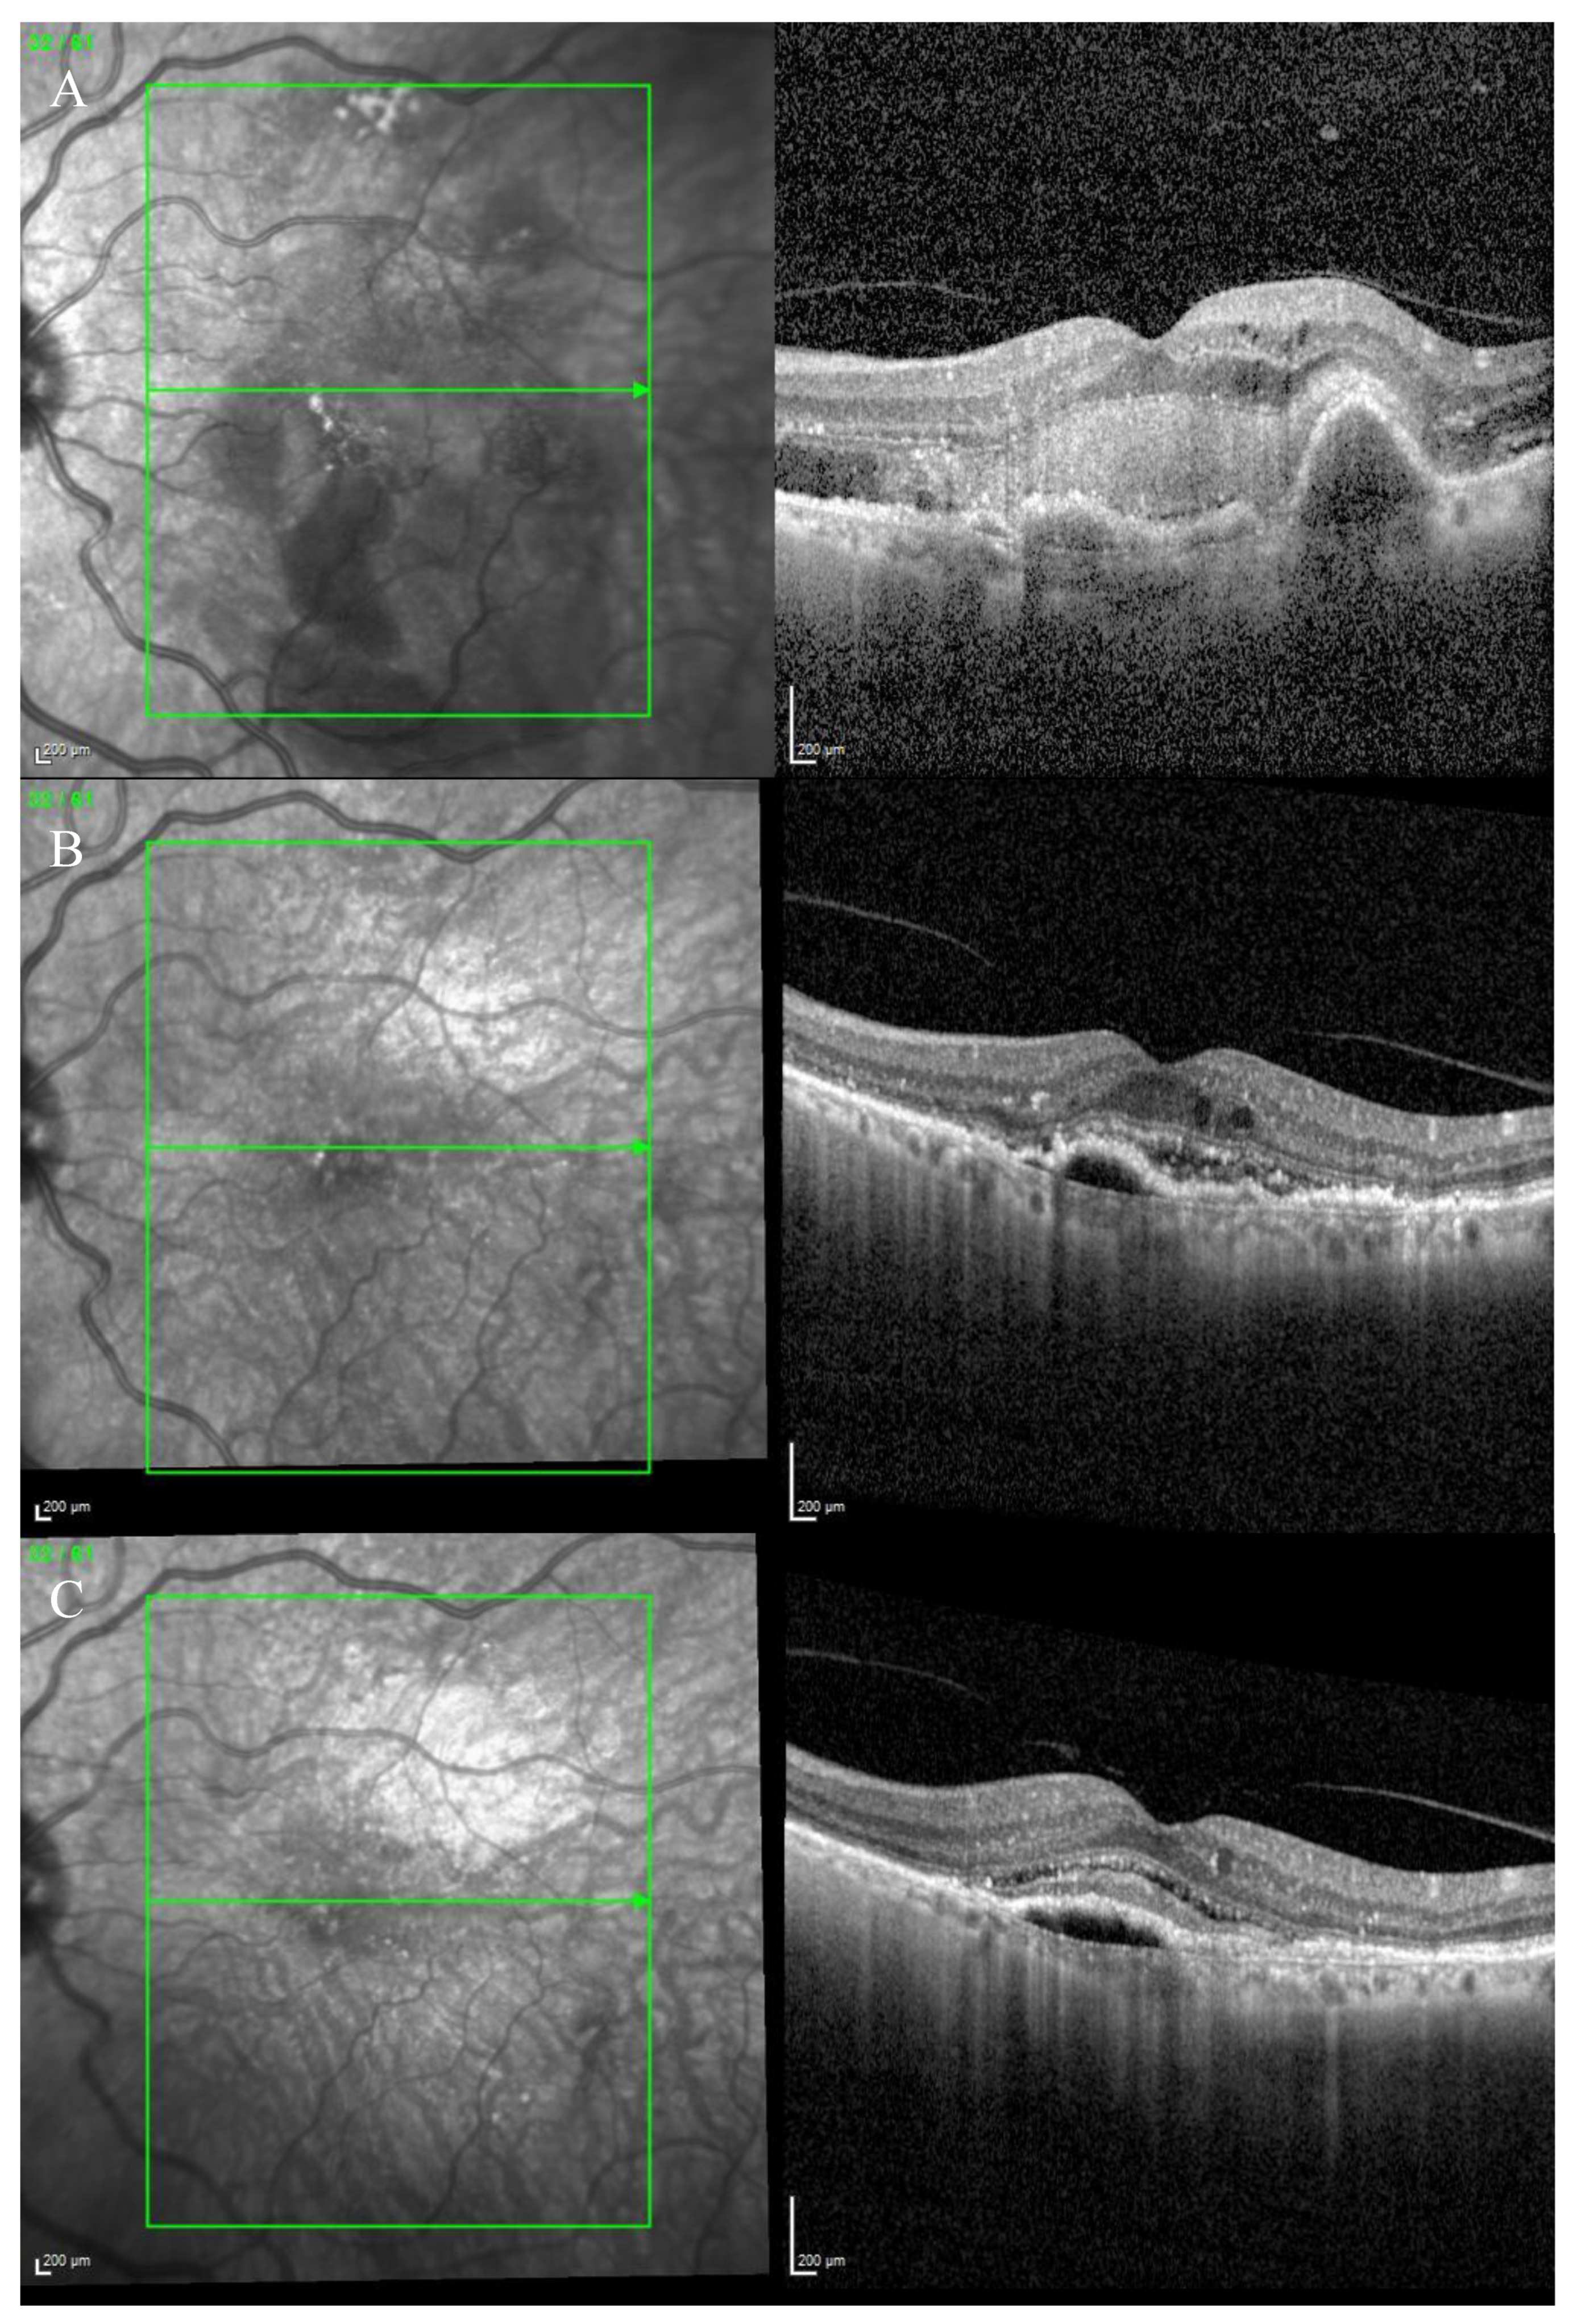

Figure 4.

Case 3. Multimodal imaging features of bacillary layer detachment (BALAD) in a patient with left eye neovascular age-related macular degeneration. (A) Optos Ultra-widefield colour shows a macular subretinal fluid with a round yellow border. (B) Spectralis MultiColor shows a yellowish lesion with subretinal fibrosis. (C) Optos Ultra-widefield autofluorescence imaging shows a macular hypoautofluorescence lesion. (D,E) Heidelberg Spectralis optical coherence tomography shows a type 1 MNV with fibrovascular pigment epithelial detachment, subretinal fluid, and a split at the myoid zone creating an intraretinal space with multiple hyper-reflective foci and a septa-like arrangement and a hyper-reflective granular band at the anterior border of BALAD. The posterior border showed a hyper-reflective thickened band. The external limiting membrane is recognizable anterior to the BALAD.

The OCT scan showed a right dry macula with drusen and a left macular type 1 MNV with a fibrovascular pigment epithelial detachment (PED), subretinal fluid, and a split at the myoid zone creating an intraretinal space with multiple hyper-reflective foci and a septa-like arrangement. A hyper-reflective granular band at the anterior border of the BALAD was reported. The posterior border showed a hyper-reflective thickened band. The ELM was intact, recognizable, and anterior to the BALAD (Figure 4D,E).

The presence of the left MNV was confirmed by an OCTA scan.

An anti-VEGF intravitreal injection T&E regimen was commenced. However, the patient was non-compliant.

In March 2022, the patient decided to stop the treatment.

During the T&E treatment, the left eye developed subretinal fibrosis (Figure 4B) and no signs of visual acuity improvement were noticed in the following visits.